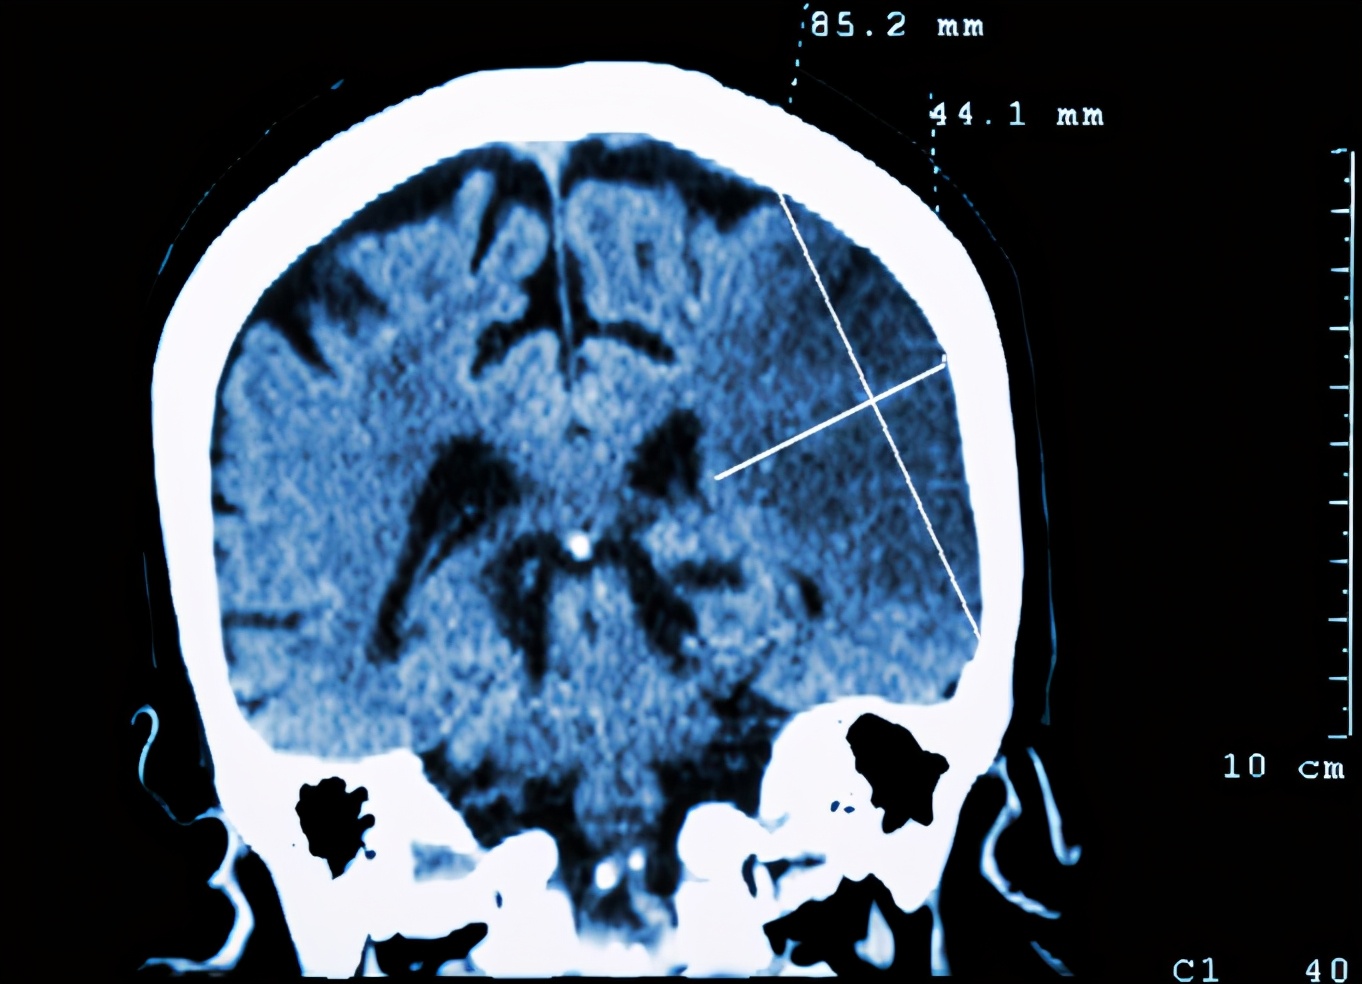

这一天李女士和往常一样给家里人准备饭食 , 突发感觉到头疼 , 随后晕倒 , 被下班的丈夫送往医院 , 最终确诊为脑梗 。

虽然李女士命被挽救回来了 , 却半身不遂 , 从此以后开始了康复之路 。

医生通过了解 , 表示李女士这次突发脑梗 , 和土豆有关 。